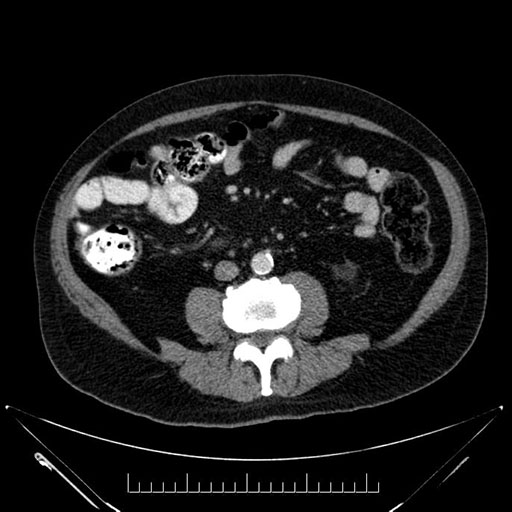

Axial - 3 months prior